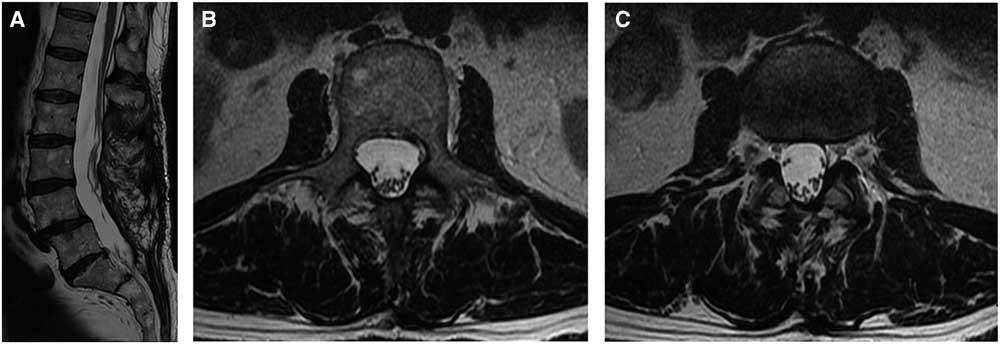

The patient was brought back for an emergency spinal decompression and durotomy. Intraoperative findings revealed an extradural hematoma at the L4-L5 level. After durotomy, the arachnoid was noted to be bulging posteriorly and xanthochromic cerebrospinal fluid was observed and released. The nerve rootlets were noticed to be anteriorly displaced. An arachnoid cyst was found from L2-L5, which was then subsequently decompressed with fenestration. Postoperatively, the patient recovered partial motor and sensory function with grade 4 motor power. After 1 year, the patient indicated he was “somewhat satisfied” with the results of the spine surgeries. His leg pain was 6 of 10 in severity, and he scored 65 of 100 on the EuroQol 5D Health Scale. Repeat MRI scans demonstrated no recurrences at 1 year follow-up (Figure 4A-C).

Figure 4 One year postoperative T2-weighted mid-sagittal (A), axial at L2 (B), and axial at L2-L3 (C) MRI scans showing the resolution of the intradural cyst.